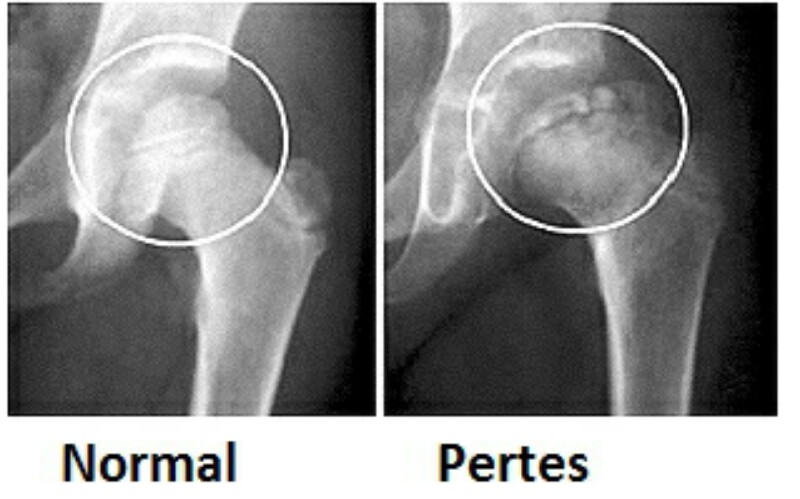

- болезнь Пертеса (остеохондропатия).

- Болезнь Пертеса

- болезнь Пертеса;